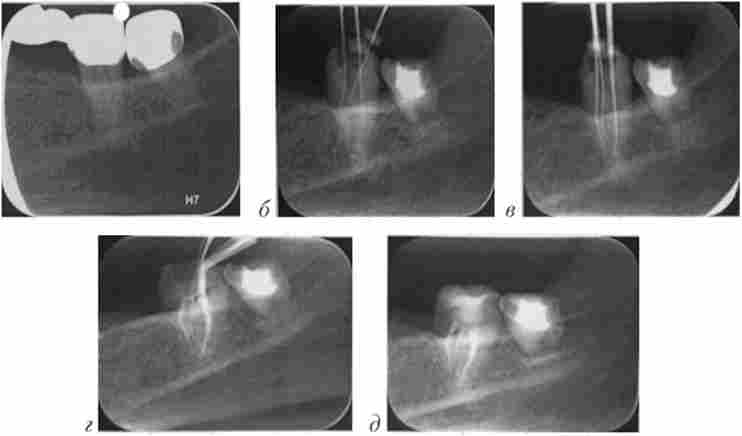

Мал. 1.7. Пацієнт X., 52 роки. Візіограмми:

а - мостовидний протез з опорою на зуби 3.6 і 3.7; б - визначення робочої довжини кореневого каналу з введеними ендодонтичними інструментами після зняття мостовидного протеза: в - контроль проходження кореневих каналів зуба 3.6 з введеними файлами; г - контроль положення центральних штифтів в каналах зуба 3.6; д - контроль пломбування кореневих каналів зуба 3.6

Раніше зроблені рентгенограми використовують в роботі. Дані рентгенографії зіставляють з клінічною картиною та даними огляду порожнини рота пацієнта. Периодонтальної щілину у гирла зубної альвеоли має ширину в середньому 2,5 мм, в пришийковій частини - 0,1 мм, у верхівки кореня - 0,2 мм.